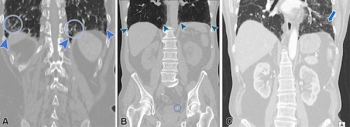

In newly published guidelines, researchers discuss the utility of CT, MRI and PET/CT in the diagnosis, staging, treatment monitoring and follow-up imaging for peritoneal metastases in patients with ovarian or colorectal cancer.